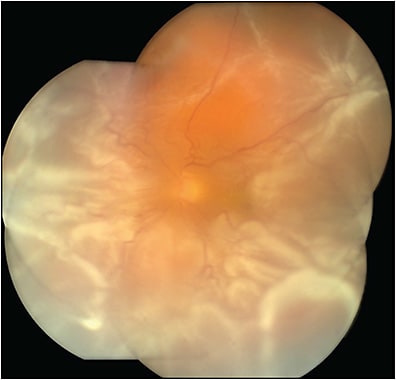

Indications for silicone oil (SO) use include tamponade for complex retinal detachments (RD) such as those with proliferative vitreoretinopathy (PVR), repair of giant retinal tears, repair of RDs in patients constrained to immediate air travel, or circumstances requiring more rapid postoperative visual rehabilitation (Table 1). Less commonly, silicone oil may be used during surgical treatment of endophthalmitis and management of postoperative hypotony. Silicone oil may itself be associated with complications such as glaucoma and keratopathy. However, even after oil removal, new issues may arise, often due to the pre-existing ocular disease, SO emulsification (Figure 1), or incomplete SO removal. This article aims to describe some potential issues and their treatment arising after silicone oil removal: recurrent RD, adhesion of oil droplets to the IOL, corneal decompensation, silicone oil-related glaucoma, and other issues leading to vision loss (Table 2).

SILICONE OIL EMULSIFICATION

Dispersion, in contrast to emulsification, is the splitting of a liquid into small bubbles. Emulsification occurs when the small bubbles are unable to coalesce with the larger bubble.6 A lipid coating forms around the smaller bubbles, preventing their re-entry into the larger bubble (Figure 3). There are multiple factors that potentially influence SO emulsification. Surfactants decrease a liquid’s surface tension within a medium, which subsequently increase the risk of emulsification. Intrinsic surfactants include serum, fibrin, and fibrinogen.6 Extrinsic surfactants include sterilization detergents present on vitrectomy tubing or the cutter or contaminants that may be on the sclerotomy cannula.6 Prior studies suggest that longer duration of SO fill,7 less complete fill,8 and use of PFO9 may also increase rates of emulsification.

Emulsified oil can adhere to an intraocular lens (IOL) or migrate into the anterior chamber (AC), causing damage to the corneal endothelium or the trabecular meshwork. While emulsification may prompt removal of SO, it is important to recognize that not all oil droplets can be removed, even with repeated fluid-air exchanges (Figure 4).